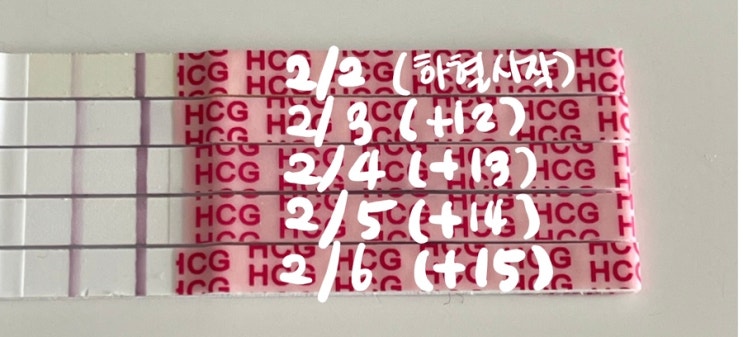

임신일기) 6주차 _ 강동구보건소 임산부선물, 비오템튼살크림, 튼살오일, 풀리오 무선다리마사지기

아기 심장소리도 듣고 했으니 카테고리를 임신일기로 변경해 보았다☺️ 내가 다녔던 난임병원 원장님께서...